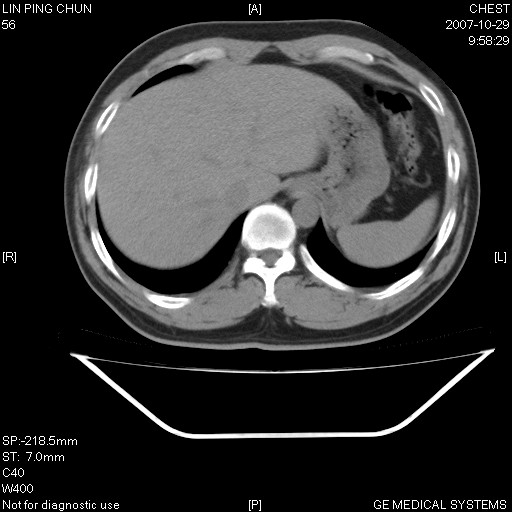

标题: CT10239:男,42Y.我自己的胸部CT扫描,今天10点突然咯血一次。

我自己胸部ct扫描,求助大家,我自己还不能给自己诊断。其他层面纵隔窗无异常。

补充:男,42y.今天10点突然咯血一次。余无异常。

左肺下叶后基底段小片结节状影,内部似见同心圆状分布条絮状影,整个病灶,质不实.局部见增粗血管影.

考虑;球形肺炎可能大.自已的身体如此重要,不进一步局部薄层及hrct?

左下肺后基底段磨玻璃样影,很多病都可以。不能吊以轻心。应该做局部增强hrct进一步检查,并严格抗炎治疗后复查或经皮活检。

左下肺后基底段小斑片泪膜玻璃样影,其内可见空泡影,边缘可见小毛刺影。建议抗炎治疗复查,肿瘤待排

老兄,我建议您把病灶做个薄层处理,靶重建,然后上传过来,您仔细看看现在的病灶特点,小病灶,边界清,内见空泡征,高度警惕细支气管肺泡癌,最好的结局就是aah(不典型性腺瘤样增生).我会密切关注您的.另外,现在您可正规抗炎治疗半月后,与3个月后复查观察病灶变化,如没有太大变化,我建议您立即手术,放心!即使是肺癌也是早期,不会影响您的生命的,祝您好运.